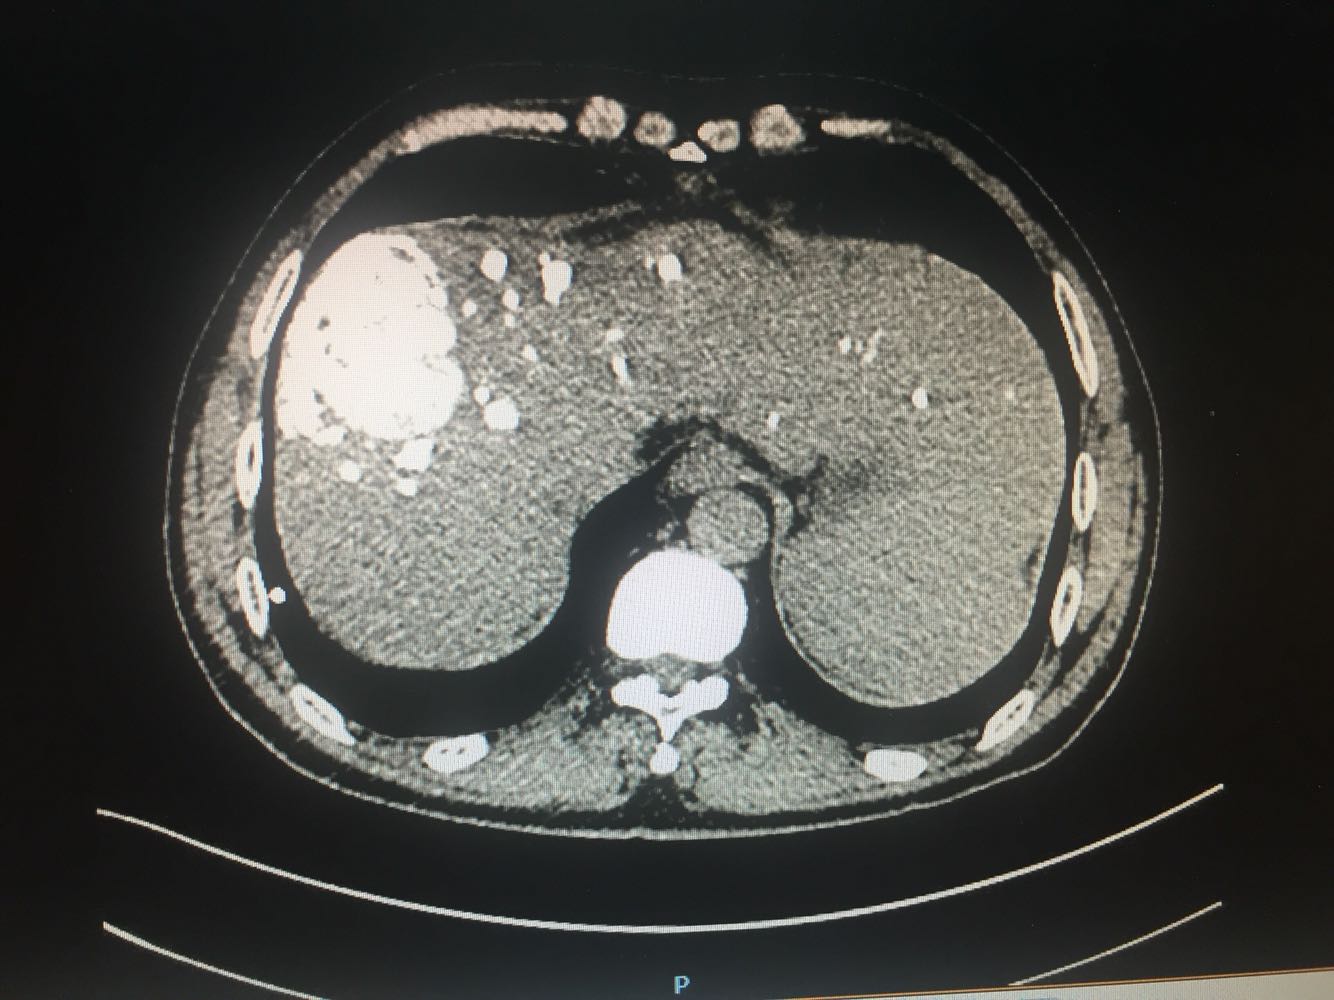

查体:体温,36摄氏度,脉搏:60次/分,呼吸,19次/分、血压,115/70mmhg,发育正常,营养欠佳,皮肤黏膜,色泽正常,双侧眼睑正常,双侧巩膜无黄染,口唇红润,双肺呼吸音清晰,心率60次/分,心律齐,心音有力,无病理性杂音。右上腹部饱满,中上腹压痛明显,肝脏肋下2cm触及,质地硬,触痛阳性,脾肋下2cm触及,移动性浊音阴性,肠音正常,双下肢无水肿 化验:血常规:白细胞计数2.9*10~9/L,中性粒细胞1.4*10~9L,红细胞计数4.03*10^12L,血小板计数76*10^9/L;生化全套。血糖4.67mol/L,总蛋白81.0g/L,白蛋白40.9g/1L,丙氯酸氨基转移酶256U/L,天门冬氨酸氨基转移酶182U,总胆红素22.0umol/L,胆碱酯酶4479U/L,Y-谷氨酰基转移酶137U/L;传染病9项:乙型肝炎病表面抗原阳性/6380,乙型肝炎病毒e抗体阳性/0.004,乙型肝炎病毒核心抗体阳性/0.008 肿瘤标志物:甲胎蛋白415.50ng/ml,乙型肝炎病毒DNA测定2.06E+07IU/ml CT:1.考虑肝右叶巨块型肝癌伴肝内多发转移,2.肝门部及腹膜后、心隔角旁小淋巴结。3.肝小囊肿。4.肝左叶増大。5.肝脏钙化灶。6.副牌。7.双肾微小囊肿

乙肝肝硬化,原发性肝癌,保肝抗病毒治疗,及TACE

出院一月后复查,行增强CT扫描,肿瘤明显缩小,肝功能正常,乙肝病毒复制转阴,建议继续口服恩替卡韦抗病毒治疗